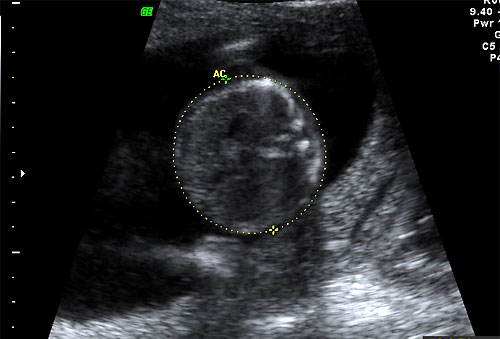

Normal AC measurement at 16 weeks |